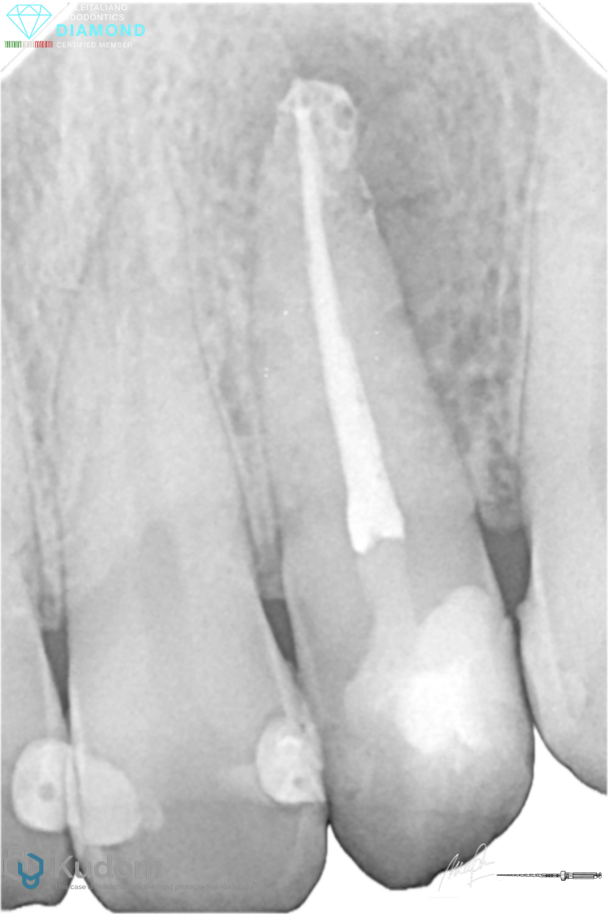

Fig. 3

After drying the canal, Bioceramic sealer was injected inside the canal slowly followed by single cone obturation technique.